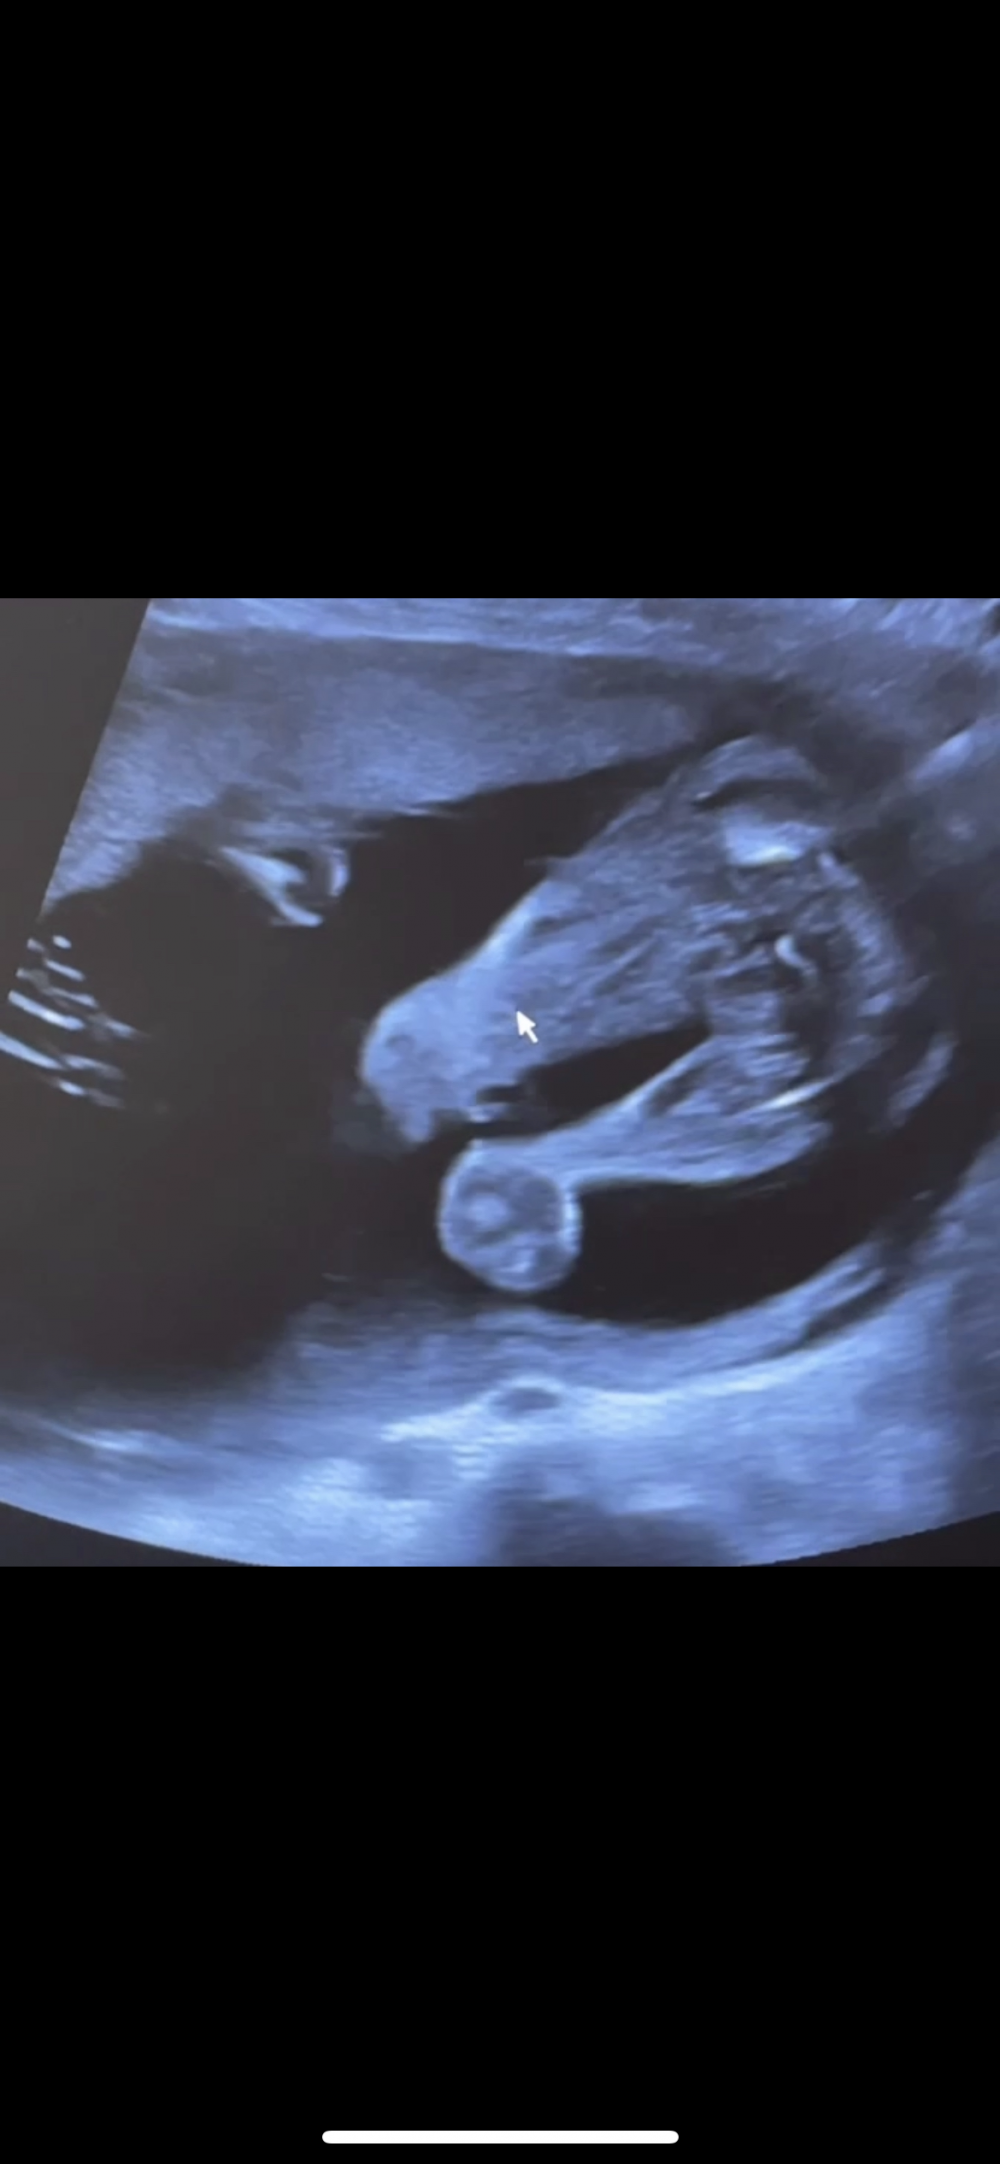

توي جيت من موعدي الحمدلله اكدت لي البنوته 😍💓

وكل شي تمام وتقول انتي باخر اسبوع بالخامس الحمدلله 😍

توي جيت من موعدي الحمدلله اكدت لي البنوته 😍💓 وكل شي تمام وتقول انتي باخر اسبوع بالخامس الحمدلله 😍